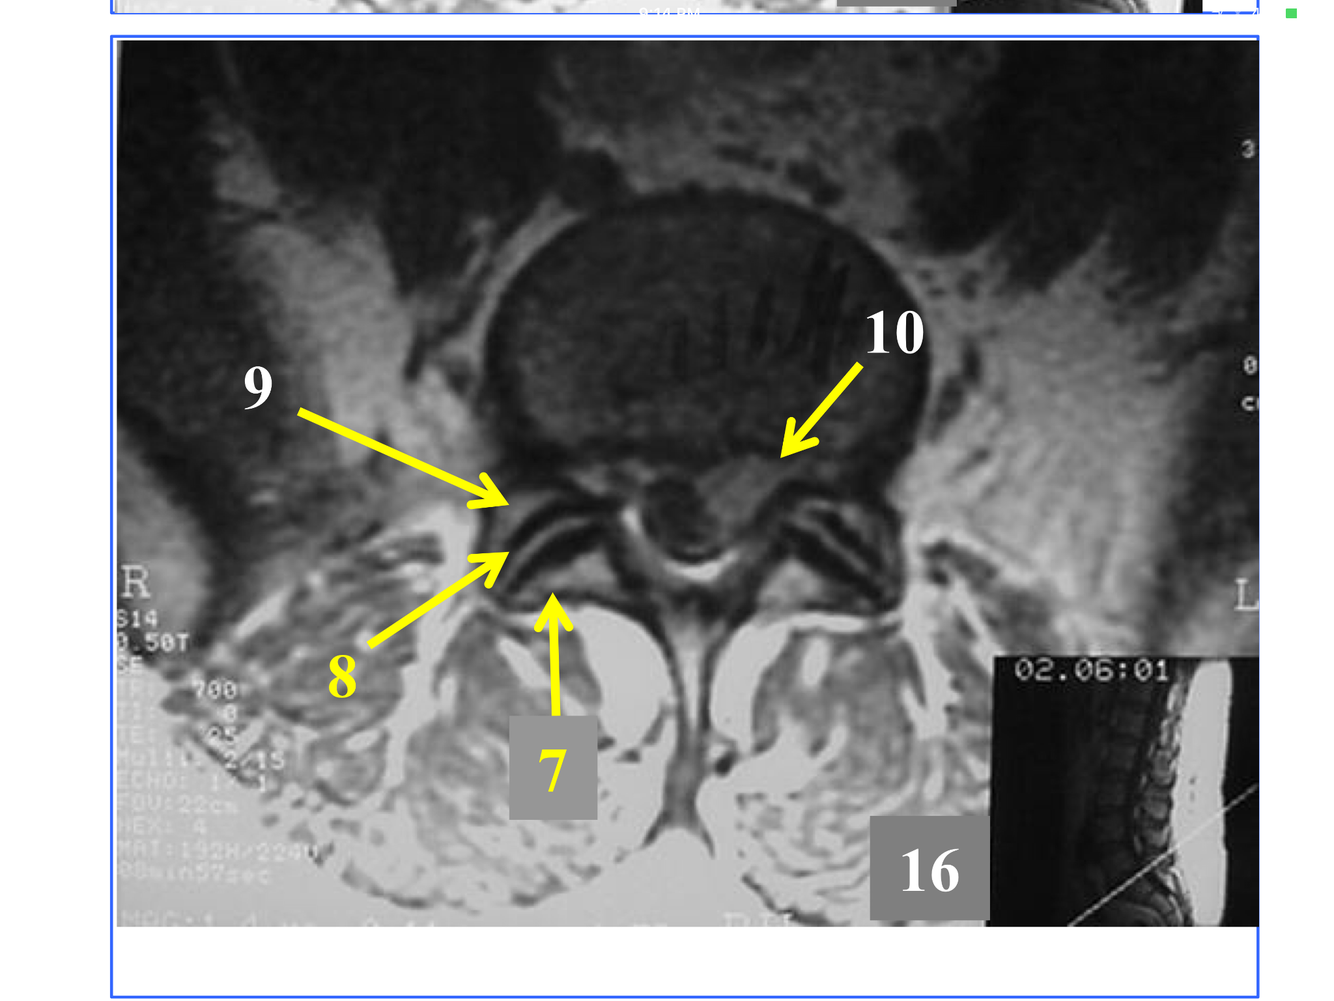

*Appears as streak as it heads fo rmidline in front of the medulla oblongata, to join the Rt vertebral and form the basilar A at the inferior and anterior to the pons.

** At the foramen magnum, entering the posterior fossa of the cranium.

**10. Rt & Lt vertebral arteries**

* Not seen in its entirety